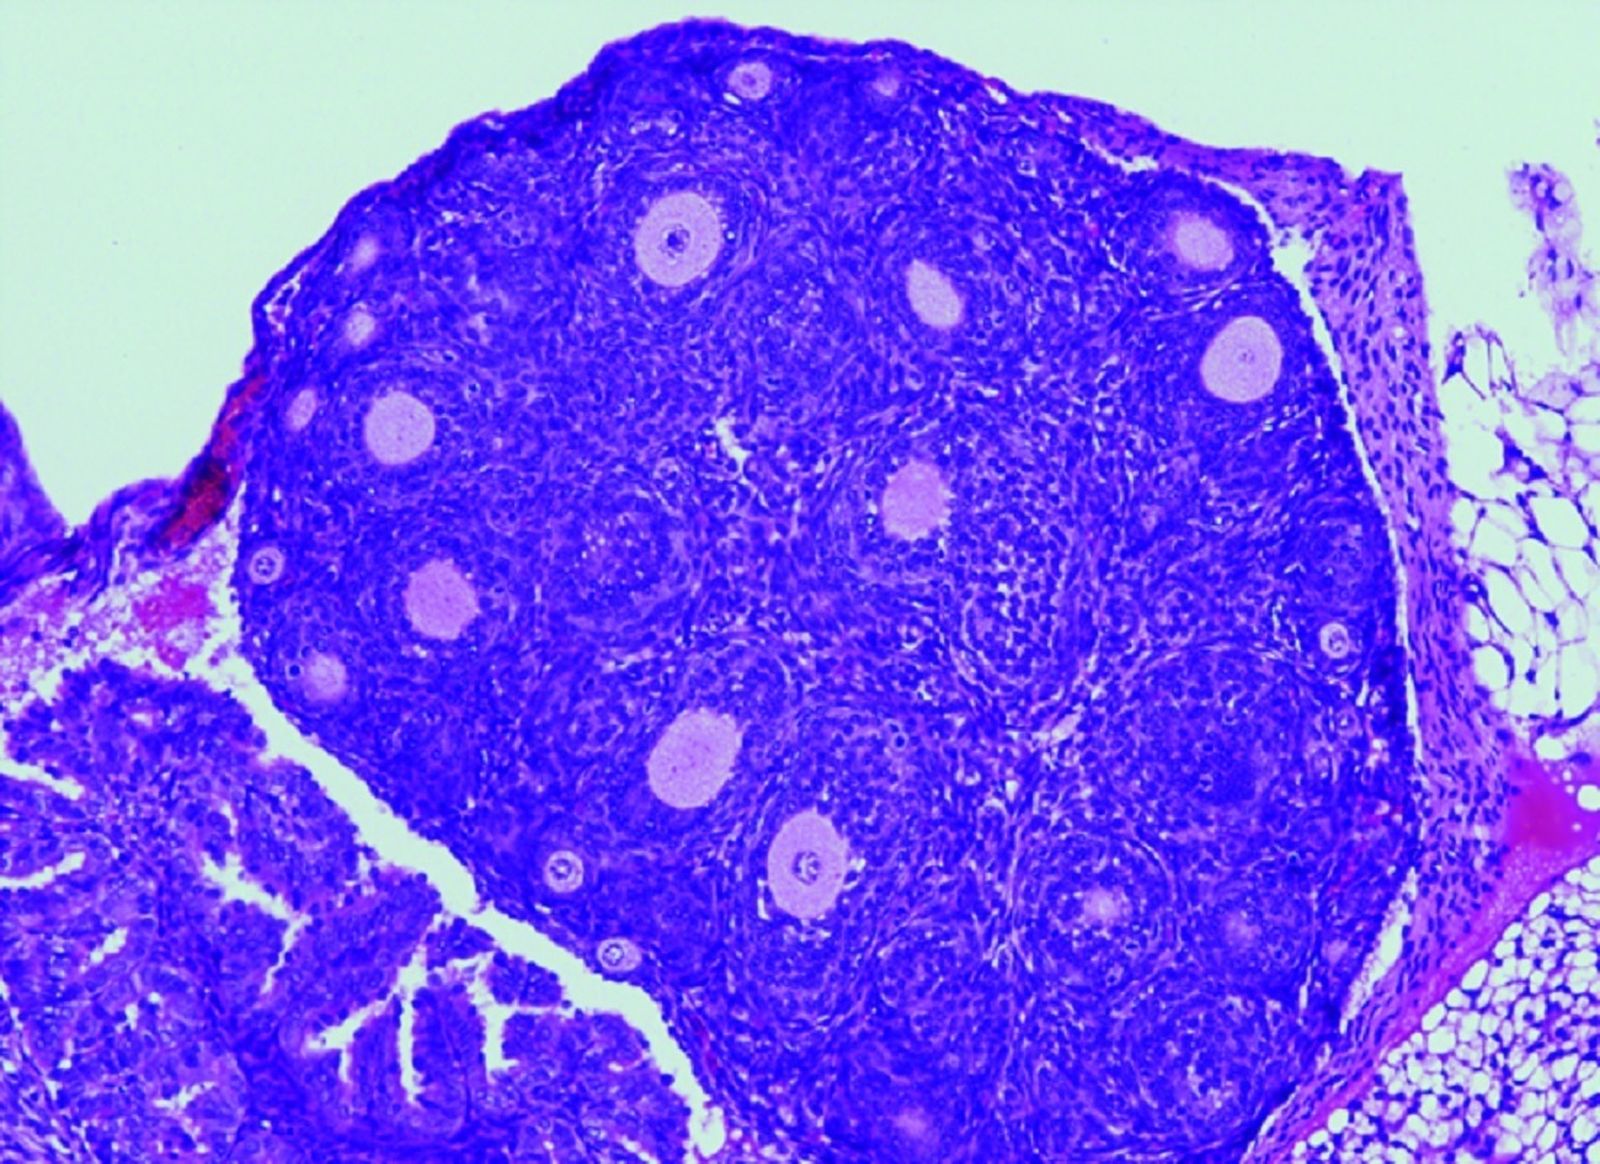

Reducción en el número de folículos ováricos en los ratones con la variante humanizada en FOXL2.

Reducción en el número de folículos ováricos en los ratones con la variante humanizada en FOXL2. / Centro De Investigación Del Cáncer (Ep)

"Nuestro grupo ha desarrollado por primera vez un modelo de ratón que alberga en su gen FOXL2 la variante C134W, presente en los tumores humanos, para así poder evaluar in vivo el papel desconocido de FOXL2 en la iniciación y desarrollo tumoral. Para nuestra sorpresa, estos ratones presentan la hipoplasia del párpado observada en el síndrome de blefarofimosis. Curiosamente, las hembras con dicha mutación presentan una fertilidad reducida y lo que es más relevante todas desarrollan AGCT espontáneamente. Es decir, progresan gradualmente de ovarios anormales con células de la granulosa aberrantes a ovarios con hiperplasia estromal y atipia, que finalmente dan lugar a la aparición de tumores ováricos en la totalidad de los animales antes de los 18 meses de edad. Por tanto, este proceso parece estar impulsado únicamente por la presencia de la variante FOXL2", ha explicado Elena Llano, de la Universidad de Salamanca.